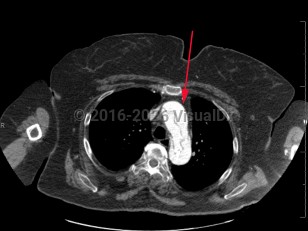

Aortic dissection is an intramural tear of the aorta. Aortic dissection is a life-threatening emergency. Tears often occur in the intimal layer of the aorta, with blood collecting in the medial layer. Back pain is the common presenting symptom, but it may also present with chest pain, dyspnea, or a new neurologic deficit. Syncope and hypotension occur less frequently. Aortic dissections most often occur in older men.

- Type A – dissection involving ascending aorta

- Type B – dissection that does not involve ascending aorta (ie, aortic arch and descending aorta)